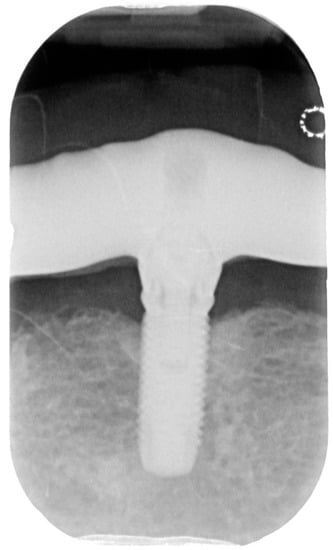

Figure 6.

X-ray of patient before treatment in position 1.1 of dental implant.

Figure 9.

X-ray of patient in 6 months after treatment.